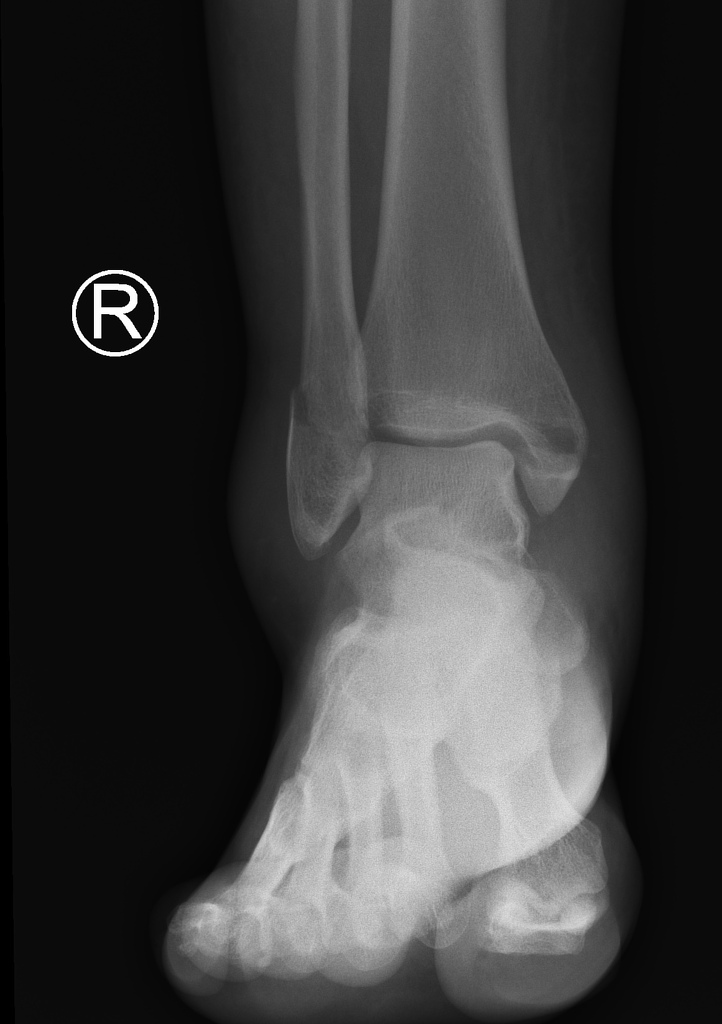

Example 3

Diagnosis

Bimaleolar fracture

Image 3: Dixon, A. Bimalleolar ankle fracture. Case study, Radiopaedia.org. https://doi.org/10.53347/rID-35590